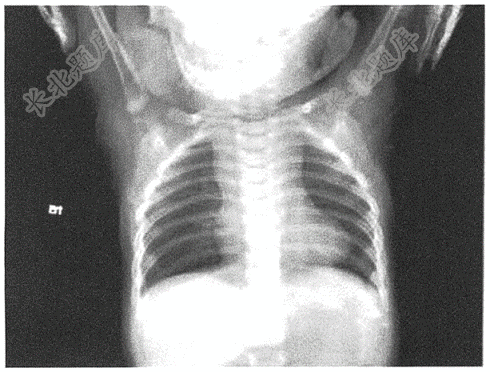

- 简答题男性患儿,1岁。发现心杂音半年来诊,口唇发绀,胸骨左缘可闻3-4Ⅲ/6收缩期杂音,P2不亢,上肢SPO₂72%,下肢SPO₂70%。胸片如图。